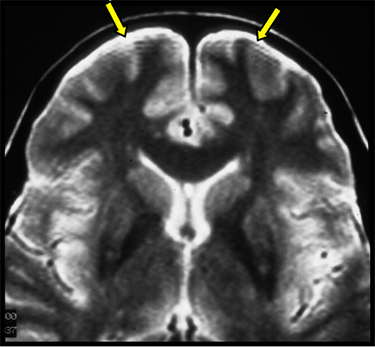

| PROPELLER- Crinkling Slight signal voids, most commonly in superior slices | ![]() | Incorrect ETL, extreme patient motion, or phase wrap |